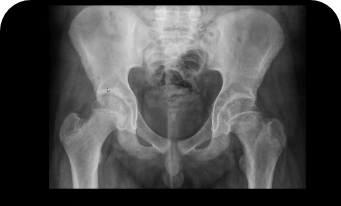

Na Ortopedia Pediátrica, o uso de técnicas modernas e abordagem personalizada são fundamentais para garantir um cuidado de excelência. Cada tratamento é cuidadosamente planejado, considerando as necessidades específicas de cada criança, desde o manejo de fraturas até correções complexas de deformidades congênitas e patologias do quadril infantil.

Displasia do desenvolvimento do quadril (DDQ)

Subluxação e Luxação do Quadril

Epifisiólise

Doença de Legg-Calvé-Perthes